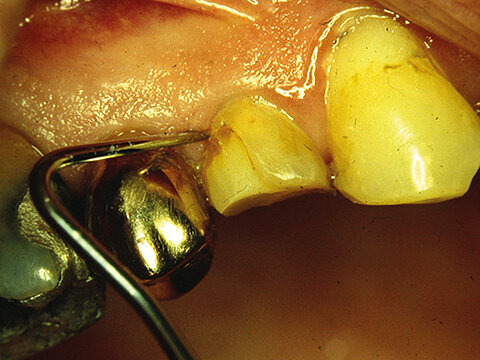

Fig 1. Blood stain at the marginal third of a composite resin filling in a premolar, accompanied with a 1-mm gap at the gingival margin. The restoration is less than 6 months old. Photo by Leo Tjäderhane

Have you ever had a Class V cavity preparation right at the gingival margin ready to be restored, when the gingiva starts bleeding heavily? Several hemostatic agents are supposed to stop bleeding, and they do – but if you even slightly touch the gingiva with your instrument the bleeding starts again. Frustrating, isn’t it? Unless you are extremely careful and very lucky, the restoration may easily be ruined (Fig. 1). At least, your day is ruined.